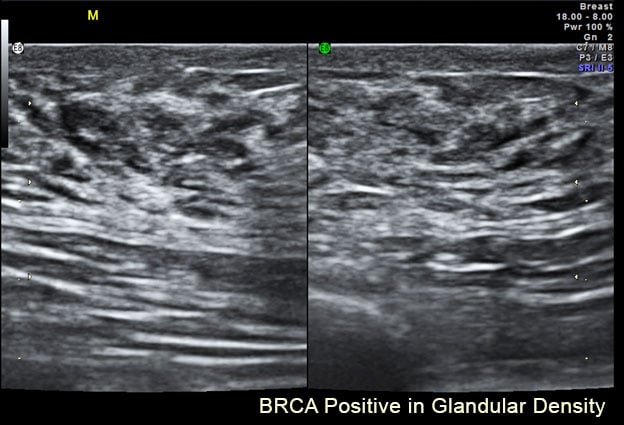

Image 3.

Another example of a dense breast shows the difference between homogeneous white versus the whitish area (see Image 3). This is filled with dark, wormy looking structures, which are the breast glands called glandular tissue. This kind secretes milk and its glands are often dilated. Both fibrous and glandular may appear similar under a mammogram as highly dense areas, but they look completely different under an ultrasound scan. Through ultrasound, we can check for tumors easily through fibrotic dense breasts because it stands out as a black region (or a black hole) within the white area. As shown in Image 3, a black hole could get lost, making it more difficult to image this type of dense breast. In this case, a solution is the use of elastography (see Image 4), which offers visual confirmation as indicated by color data. Elastography can measure tissue density (its hardness or elasticity) within the glandular breast tissue.

BRCA Positive in Glandular Density.

This tissue type is more common in the under-40 age group and is associated with other glandular proliferation such as endometriosis and is reportedly linked to dermal inflammation. In published reports, comparative studies between fibrous and glandular breast tissue studies remain limited. We are observing (especially in the younger age groups) expanding reviews of these types of tissue density aligned with the rates of breast cancer to confirm the rate of malignancy in tissue alteration from normal.